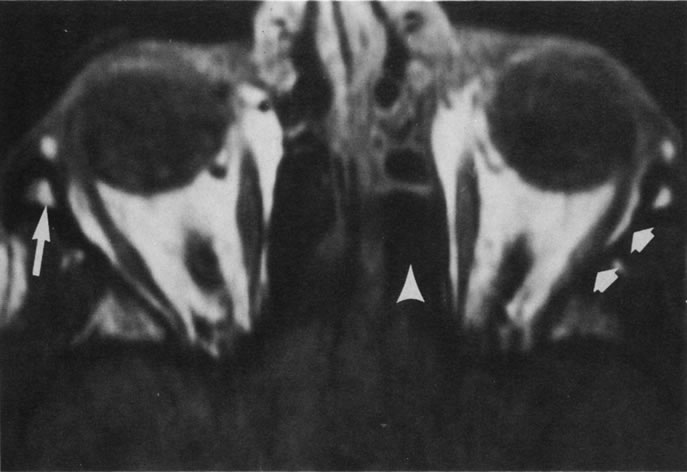

Tl relaxation time is the time required for the energized nuclei to give up the excess energy that was acquired from the RF pulse (high-energy state) and re-establish equilibrium (low-energy state) with the main magnetic field. The excess energy is released by these excited nuclei to the surrounding molecular environment, or lattice, and results in T1 relaxation, also called spin-lattice relaxation time. In different biologic tissues, hydrogen has a Tl ranging from a few hundred milliseconds to a couple of seconds. This range exists because local tissue factors affect the ability of specific protons to give up energy to the surrounding tissues. For example, hydrogen atoms attached to the carbon atoms of fat molecules relax much more rapidly than those attached to the oxygen atoms of water molecules. Viscosity, concentration, temperature, and molecular environment of the hydrogen atoms in the tissues also affect the T1 relaxation time. On a T1-weighted orbital image, fat, which has a very short T1 relaxation time, yields a high-intensity signal; the rectus muscles, which have an intermediate T1, yield an intermediate-intensity signal; and the vitreous, which has a long T1, yields a low-intensity signal (Fig. 8).5,8,16

Application of a 90° RF pulse brings the excited nuclei into phase so that the net vector of their magnetic moments is directed perpendicular to the static magnetic field. Shortly thereafter, the magnetic moments of the nuclei spread out and point in different directions, leading to a loss of phase coherence and a resultant decay in signal intensity amplitude. The T2, or spin-spin relaxation time, is the rate of decrease in the signal of these excited nuclei as a result of the interaction and transfer of energy to unexcited adjacent nuclei. T2 ranges from a few milliseconds to a few hundred milliseconds and, for a given tissue, is always less than the Tl relaxation time. T2-weighted orbital images are easily recognized by a high-intensity signal from the vitreous (Fig. 9).5,8,16